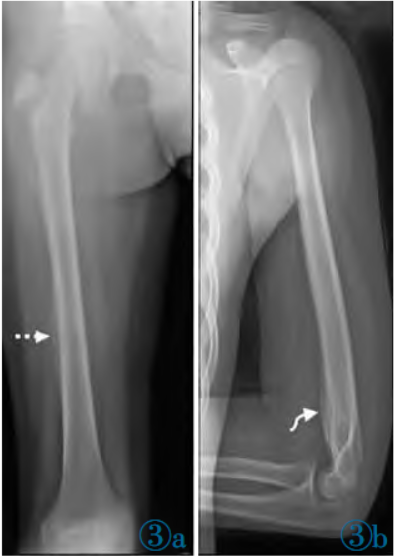

患者为评估骨显像新发现病灶,遂行X线检查。X线示:右股骨中下段(虚线箭头A)和左肱骨远端(曲线箭头B)可见不规则骨质破坏,骨骺板增宽,内见点状高密度影,邻近骨质可见骨膜反应,周围软组织肿胀(图3a,3b)。患者行右胫骨远端穿刺

图3X线:右股骨中下段(虚线箭头A)和左肱骨远端(曲线箭头B)可见不规则骨质破坏,骨骺板增宽,内见点状高密度影,邻近骨质可见骨膜反应,周围软组织肿胀。病理组织学HE染色:慢性炎症细胞浸润伴坏死,符合慢性③a③b骨髓炎表现。